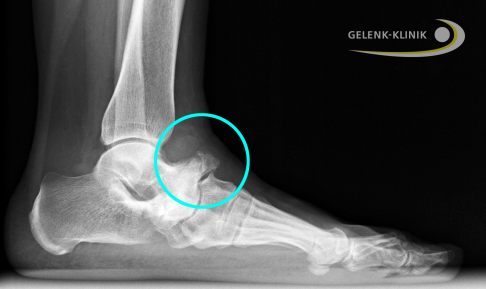

Röntgenbild seitlich: Im späten Stadium des Müller-Weiss-Syndroms sind das Fersenbein (Calcaneus) und das Fußlängsgewölbe abgesunken. Im Kreis ist das nach oben heraustretende Knochenstück des Kahnbeins sichtbar. Die Schädigung betrifft bereits das nachfolgende Gelenk zwischen Kahnbein und Keilbein. © Gelenk-Klinik

Die Röntgenaufnahmen zeigen bei fortgeschrittenem Müller-Weiss-Syndrom ein abgeflachtes Kahnbein, dass zunehmend nach innen (medial) und Richtung Fußrücken (dorsal) verdrängt wird. Das Kahnbein kann wie ein Komma erscheinen. Durch den Umbau (Sklerosierung) des abgestorbenen Knochenbereichs erscheint das Kahnbein auf der Röntgenaufnahme deutlich dichter und kompakter. In frühen Stadien der Erkrankung ist die Röntgenuntersuchung nicht hilfreich, da die knöchernen Veränderungen noch nicht sichtbar sind.